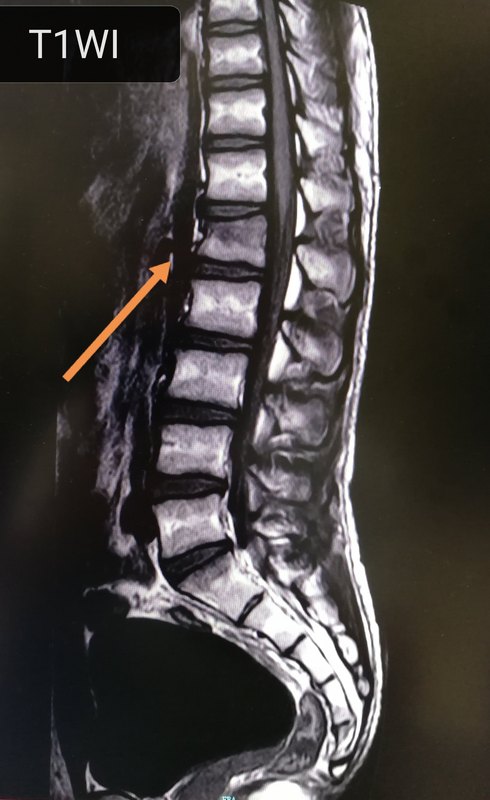

病史:外傷致腰背部疼痛、活動(dòng)受限1小時(shí)。病史明確,表現(xiàn)典型,呈楔形改變,前緣欠連續(xù),壓脂像L1椎體骨髓水腫明確。磁共振能確定新鮮骨折引起的椎體骨髓水腫。診斷:第一腰椎(L1)壓縮性骨折(新鮮)